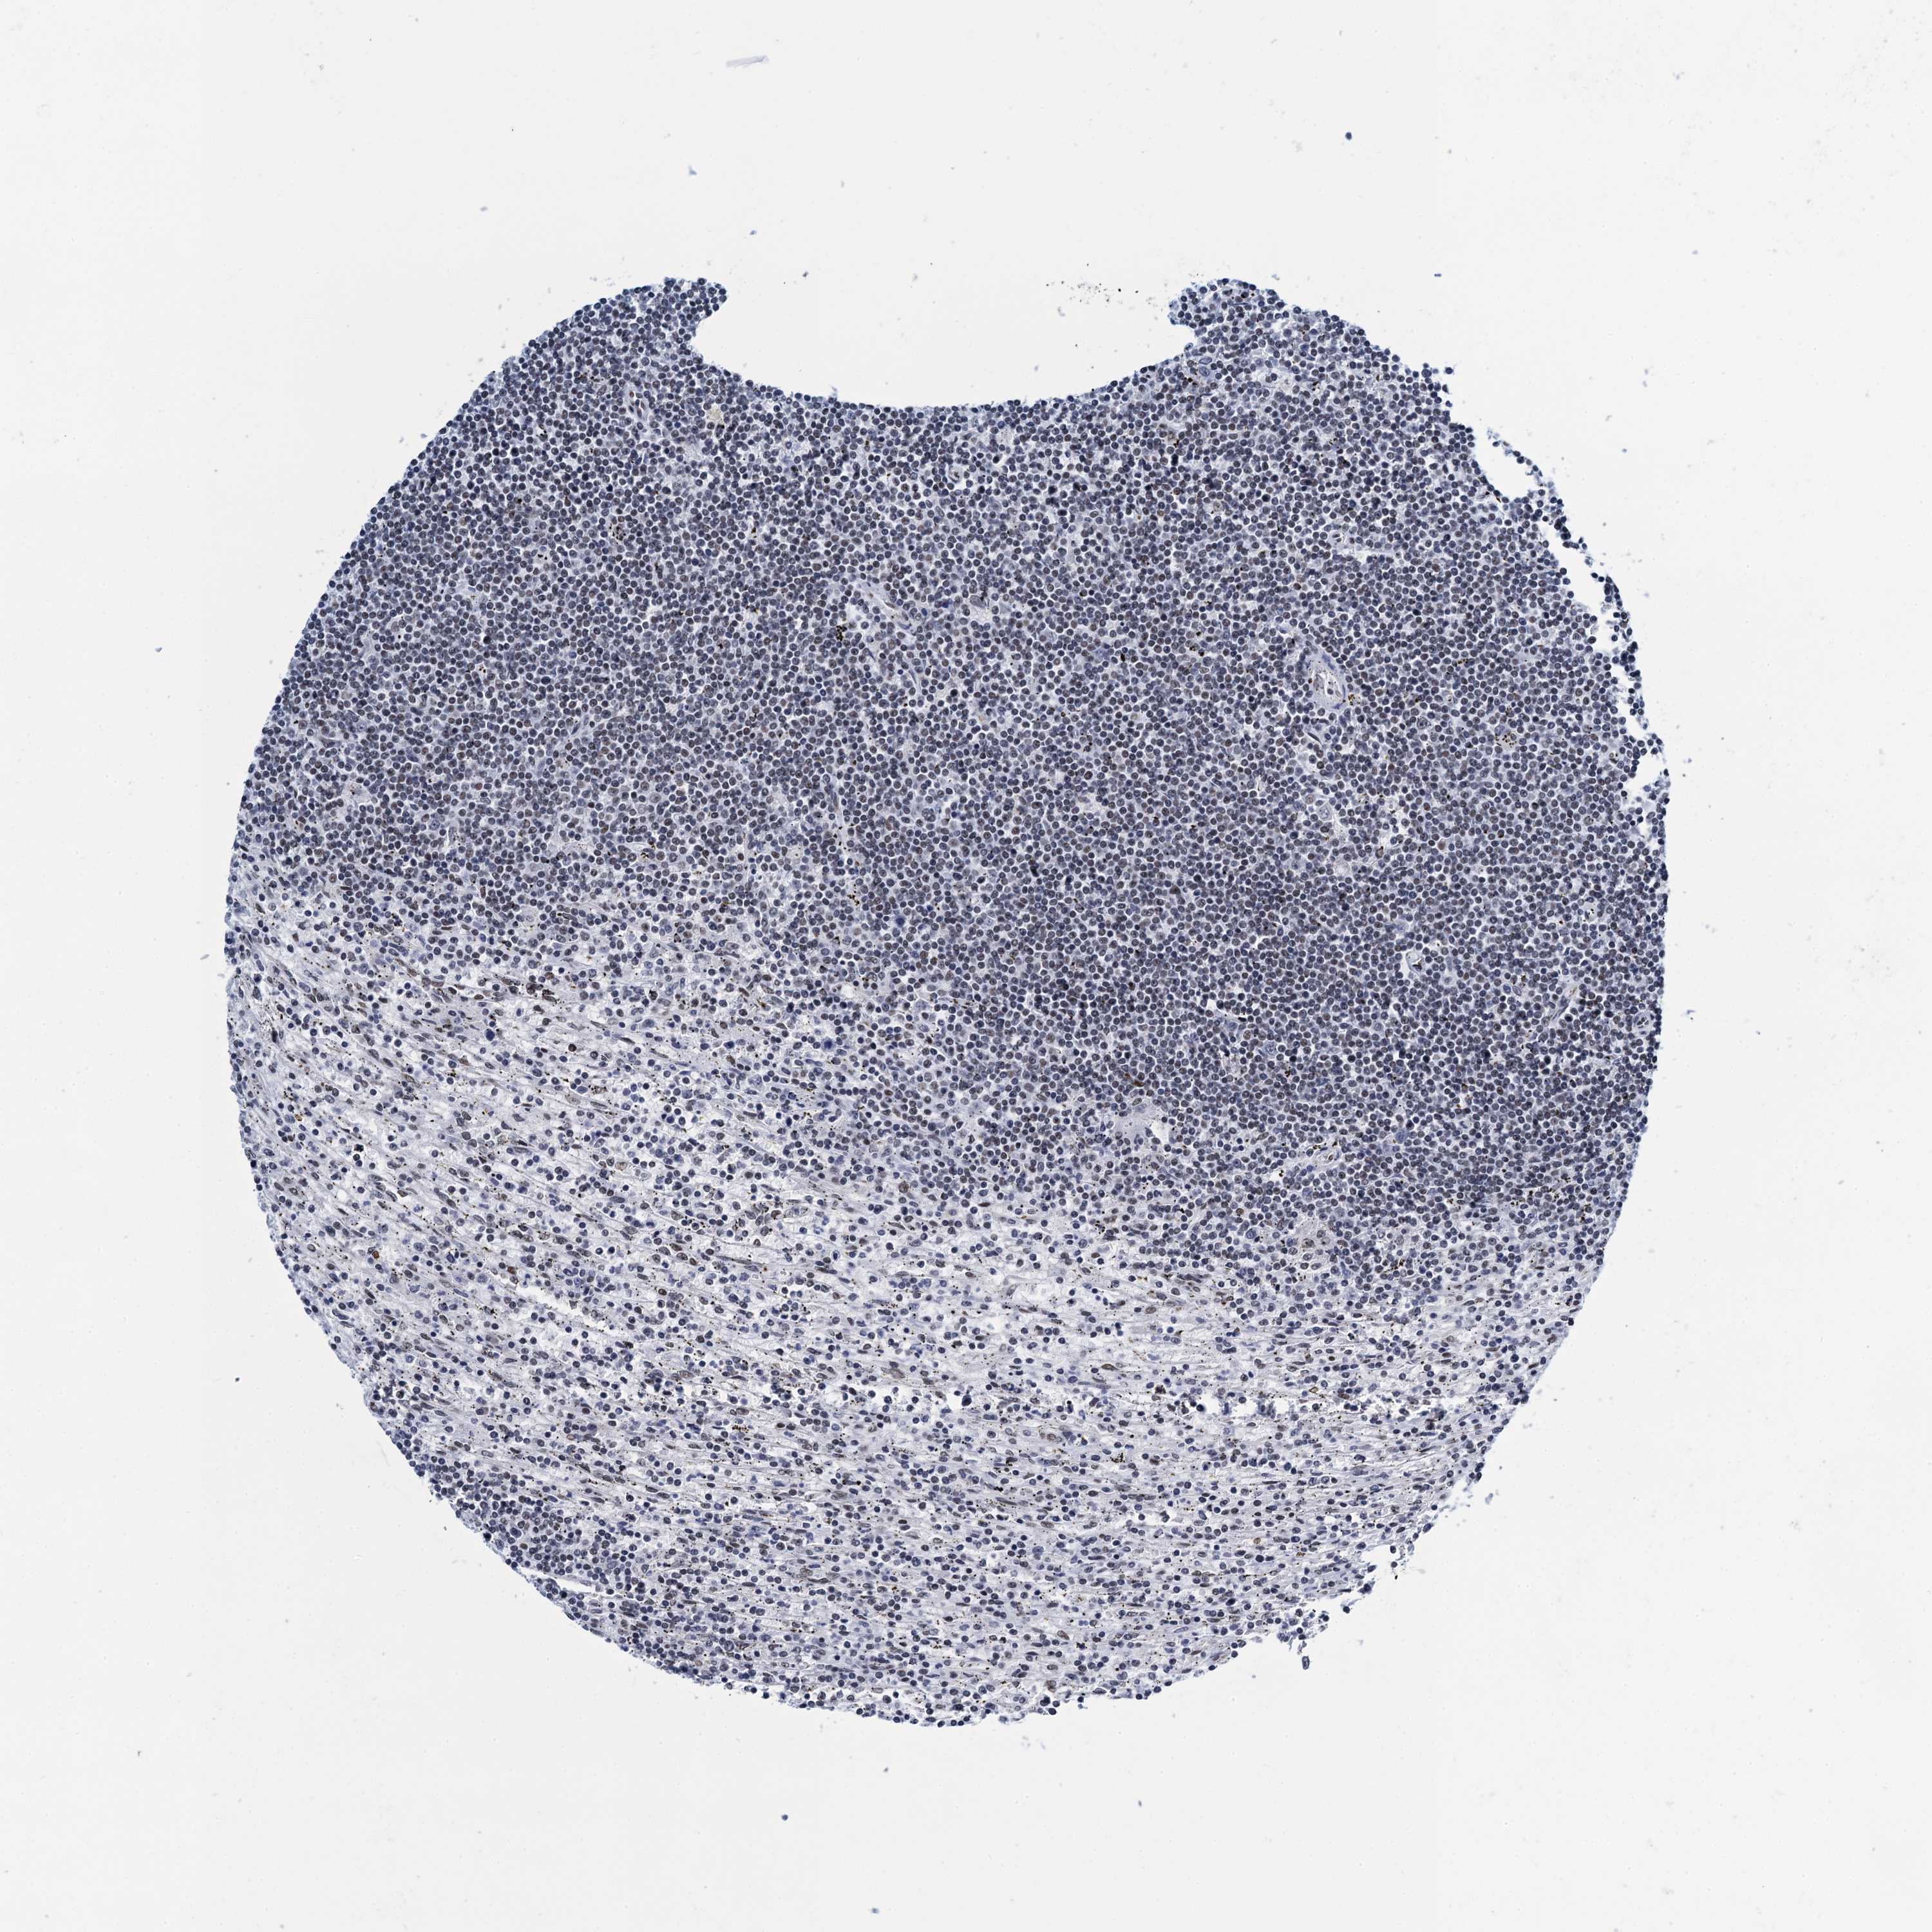

LYMPHOMA - Protein expressioni

A mouse-over function shows sample information and annotation data. Click on an image to view it in a full screen mode. Samples can be filtered based on level of antibody staining by selecting one or several of the following categories: high, medium, low and not detected. The assay and annotation is described here.

Antibody stainingi

Antibody staining in the annotated cell types in the current human tissue is reported as not detected, low, medium, or high, based on conventional immunohistochemistry profiling in selected tissues. This score is based on the combination of the staining intensity and fraction of stained cells.

Each image is clickable and will lead to virtual microscopy that enables deeper exploration of all samples and also displays staining intensity scores, fraction scores and subcellular localization as well as patient and tissue information for each sample.

Antibody HPA041632

Hodgkin's disease, NOS

Malignant lymphoma, non-Hodgkin's type, High grade

Malignant lymphoma, non-Hodgkin's type, Low grade